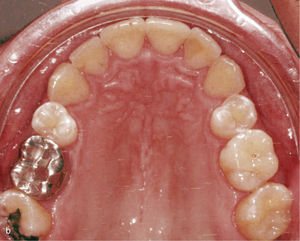

La expansión transversal constituye una alternativa a la reducción de esmalte interproximal para corregir apiñamientos y para dotar a las arcadas de un aspecto armonioso. La figura 4a muestra un maxilar estrecho en el plano transversal y dientes muy rotados y apiñados en el sector anterior. En este caso fue posible lograr una arcada armoniosa utilizando anclajes en los dientes 14, 13, 23 y 24 con ataches verticales, expansión transversal, protrusión del diente 21 y reducción del esmalte interproximal (fig. 4b).

Sector anterosuperior con dientes 11 y 21 en mesioversión y triángulo negro interdental (a). Se colocaron ataches rectangulares verticales en los dientes 11 y 21 y en los anteriores adyacentes. Resultado del tratamiento después de enderezar los dientes 11 y 21 y de cerrar el triángulo negro (b).